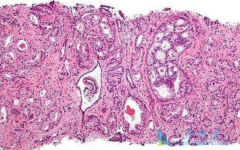

据相关的数据统计, 前列腺癌 在我国的发病率呈现不断上升的趋势,年增长速度已经超过了5%,位居所有肿瘤增长率的前两位。根据前列腺癌的不同分期,患者的治疗方式和预后也有所不同。精准判断前列腺癌的分期,可以帮助专业的医生来确定癌肿的范围和活性 ...